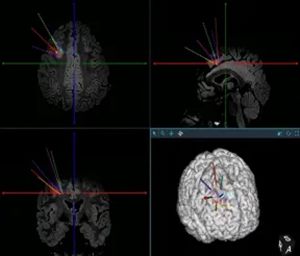

经过详细的术前评估,神经外科二病区李培栋主任和李信晓博士团队设定了精密的手术方案,精准植入了6根颅内电极,刚好将病灶完整包围。

这,就是立体定向脑电图(SEEG)技术。

在接下来的几天里,通过电极直接记录到了发作期异常放电的源头,进一步验证了它就是真正的“元凶”。更关键的是,电极的覆盖范围足够精密,明确了病灶边界,且避开了重要的功能区——这意味着,我们不仅能抓住它,还能就地解决它。

有了SEEG提供的精确“地图”,随即通过电极对这块仅几立方毫米的脑组织进行了“射频热凝毁损”。